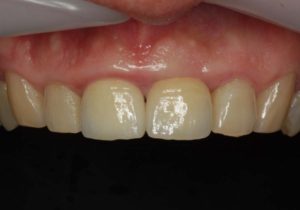

どのように変わったか、下の写真をご覧ください。

- 術前

- 術後